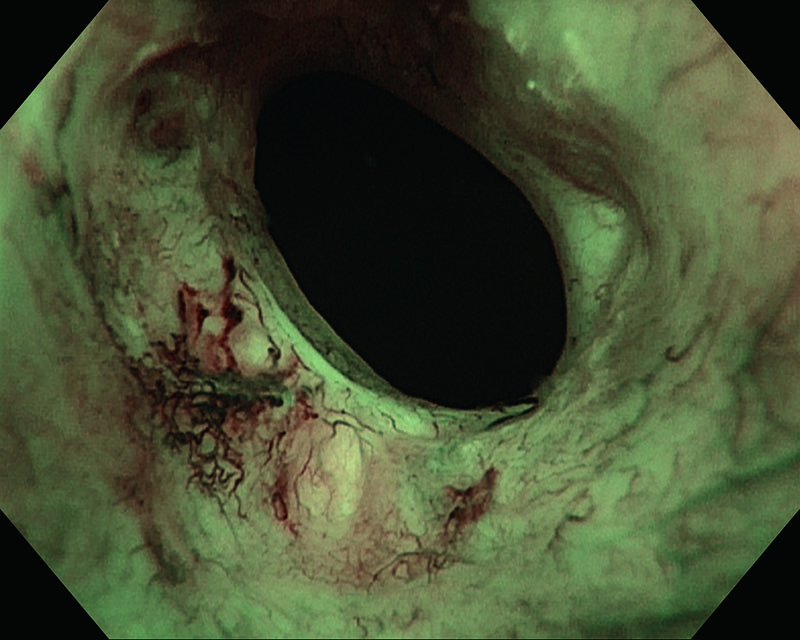

Mucosa congestiva del trígono de la vejiga, 28 años, mujer

Mucosa congestiva del trígono vesical. NBI realza el área hipervascularizada. La histología mostró pTa, bajo grado (G2).